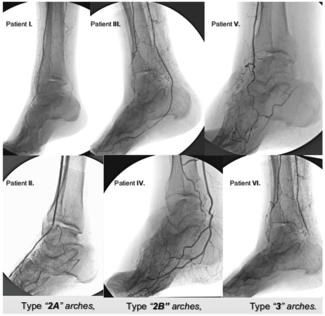

Vlad Adrian Alexandrescu, MD, PhD; Arnaud Kerzmann, MD; Evelyne Boesmans, MD; Larissa Leruth, MD; Geneviève Mignolet, MD; Jean-Olivier Defraigne, MD

It appears that novel guidelines may be needed to assess the ischemic pedal flow. These novel diagnostic scales should associate multilevel arterial branching disease classification, standardized calcification indexation, and commonly...